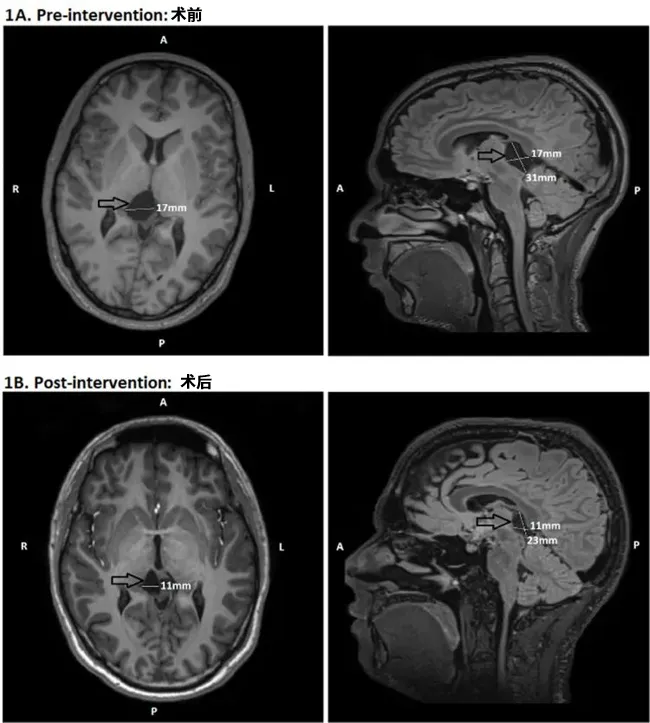

头颅MRI检查揭示意外发现:蛛网膜囊肿压迫丘脑及顶盖区域——该区域为调节警觉性与注意力的关键神经中枢(图2A)。这一结构异常可能是患者长达十年嗜睡症状的根本原因。

接受神经外科显微开窗术后两个月,囊肿压迫得到解除,脑脊液循环恢复正常。术后六个月MRI复查显示囊肿体积显著缩小(图2B)。更重要的是,患者自觉日间困倦感基本消失,注意力集中能力明显改善,Epworth评分从13分降至6分(正常范围)。客观睡眠潜伏期测试证实其维持清醒的能力获得显著提升。